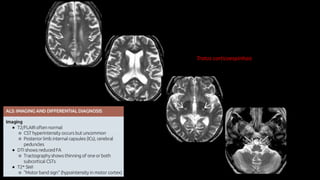

Creutzfeldt-Jakob

• 0,25 a 2 casos/milhão

• Tríade

• Demência rapidamente progressiva

• Mioclonia

• EEC com padrão periódico de onda aguda seguida por onda lenta (complexos

ponta-onda) em frequência aproximada de 1/seg

• Sobrevida média inferior a 1 ano após início dos sintomas.

Koeller et al., Radiographics. 2017

Encefalopatias Espongiformes Transmissíveis

Doenças Priônicas

• Perda neuronal rapidamente progressiva com degeneração

espongiforme, gliose, perda sináptica e ausência de resposta

inflamatória.

• Acentuada atrofia difusa do parênquima cerebral e cerebelar.